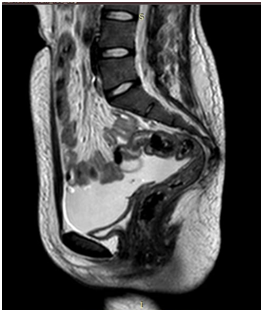

ECG showed signs of LVH. Echocardiography affirmed concentric left ventricular hypertrophy with moderate mitral regurgitation, aortic regurgitation and mild tricuspid regurgitation with pulmonary hypertension.MRI abdomen and pelvis was done and revealed absent uterus blind ended vaginal pouch 3cm.Ovaries could be visualized showing mature follicular activity with normal urinary bladder, urethra, rectum and anal canal, but bilateral average sized grade III pathological kidneys (Figure 1). To investigate the cause of renal failure, renal biopsy was done and revealed advanced extensive renal amyloidosis.

Figure 1 MRI abdomen and pelvis was done and revealed absent uterus blind ended vaginal pouch 3cm.Ovaries could be visualized showing mature follicular activity with normal urinary bladder, urethra, rectum and anal canal.